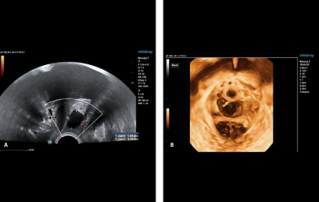

Endocavity ?? ?? ?? ???(DE10-3WU, Resona 7, Mindray)? ??? ??? ???? ?? ?? ????(Levator ani nuscle)? ??? ???. ???? ?? ??? 3~4mm? ????, ???(levator hiatus) ?? ?? - 6.13cm, LUG1(??? m ??? ??. Bulbocavernosus) ŌĆō 2.95cm ? LUG2 ŌĆō 3.15cm(?? 2.5cm ??)